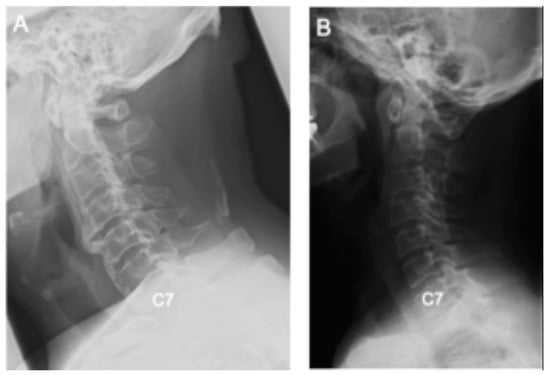

Differences in Demographic and Radiographic Characteristics between Patients with Visible and Invisible T1 Slopes on Lateral Cervical Radiographic Images

- Park, B.J.; Gold, C.J.; Woodroffe, R.W.; Yamaguchi, S. What is the most accurate substitute for an invisible T1 slope in cervical radiographs? A comparative study of a novel method with previously reported substitutes. J. Neurosurg. Spine 2021, 1, 1–7. [Google Scholar] [CrossRef] [PubMed]

- Tamai, K.; Buser, Z.; Paholpak, P.; Sessumpun, K.; Nakamura, H.; Wang, J.C. Can C7 Slope Substitute the T1 slope?: An Analysis Using Cervical Radiographs and Kinematic MRIs. Spine 2018, 43, 520–525. [Google Scholar] [CrossRef]